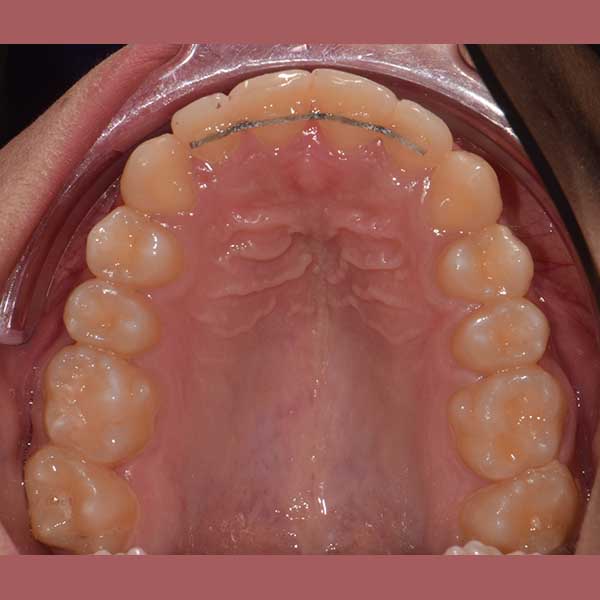

AFTER

بعد دراسة دقيقة للحالة، قرر الدكتور خالد الكاتب أن العلاج ممكن بالكامل بدون قلع أي أسنان. تم الاعتماد على تقويم الدايمون (ذاتي الربط)، والذي يشتهر بقدرته على توسيع الفكين بفعالية وتوفير المسافة اللازمة لرصف الأسنان وإنزال الناب المرتفع إلى مكانه الصحيح.

كما تظهر الصور، تم حل مشكلة الازدحام بالكامل وتم رصف جميع الأسنان بشكل مثالي. استقر الناب العلوي في مكانه الطبيعي ضمن القوس السني، وأصبحت الأسنان السفلية متراصة وسهلة التنظيف. النتيجة هي ابتسامة جميلة وصحية منحت صديقتنا الشابة الثقة التي تستحقها.